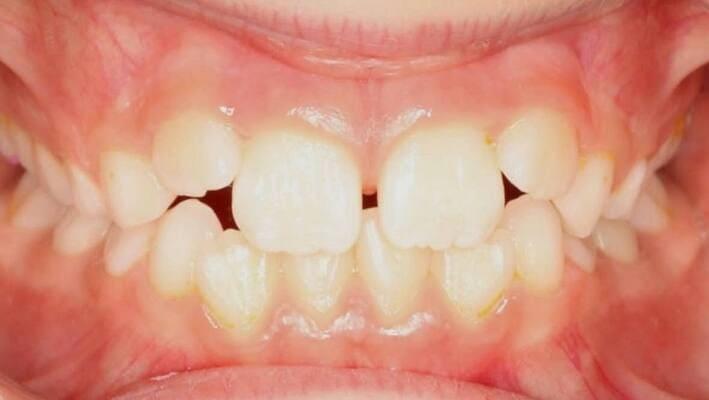

Пацієнт 2 років, уражено десять зубів, шість із яких потребують покриття коронками. В зв’язку зі значним об’ємом та складністю лікування прийнято рішення про лікування в умовах анестезіологічного забезпечення. Раніше була спроба пролікувати ці зуби застарілими методами, які не тільки не є ефективними відносно лікування, а ще і додають дитині комплексів через характерне фарбування зубів. Через високи естетичні вимоги дитини і батьків було прийнято рішення покривати естетичними цирконієвими коронками, як передні так і бічні зуби. Через 2,5 години дитина без інфекції в порожнині рота, з відновленим здоров’ям та естетикою посмішки може кусати, жувати, посміхатись без болю та дискомфорту. Останнє фото через 2 роки після лікування, оскільки естетичні коронки в дитячій стоматології - це надійність, естетика та функція.